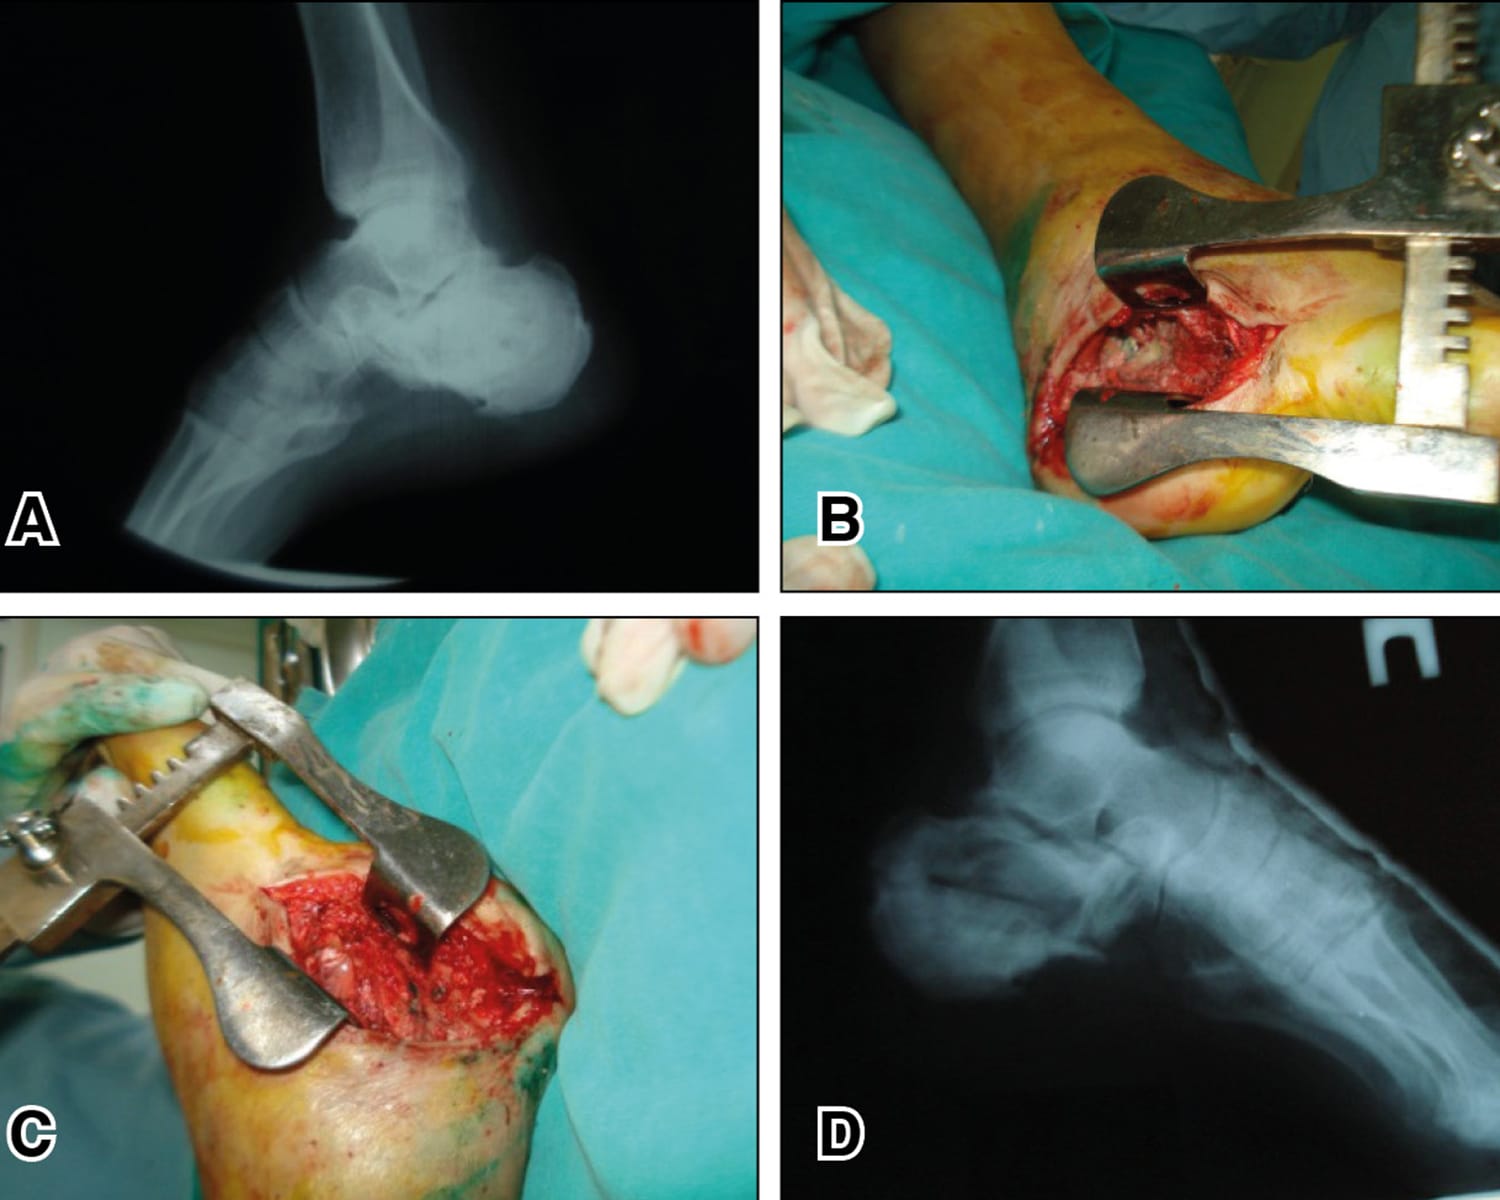

The clinical contributions in this issue address two principal domains. Musculoskeletal infection is examined through a case report on septic arthritis of the native hip caused by Granulicatella adiacens, complemented by a literature review, and a case series investigating surgical options and outcomes in calcaneal osteomyelitis. The issue further addresses revision of total hip arthroplasty, presenting an epidemiological multicentre analysis of 963 patients in France alongside an evaluation of dual mobility systems as a reconstructive strategy in revision settings.